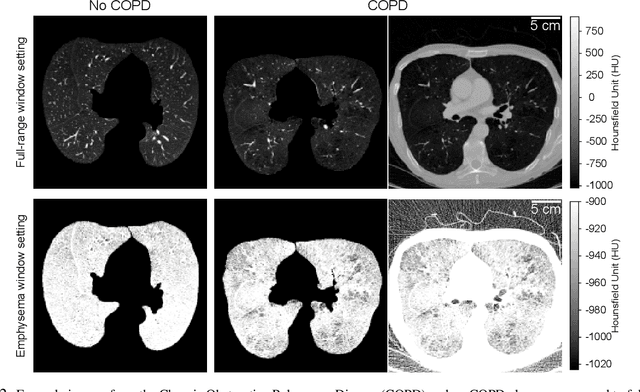

Abstract:Chronic Obstructive Pulmonary Disease (COPD) is a leading cause of death worldwide, yet early detection and treatment can prevent the progression of the disease. In contrast to the conventional method of detecting COPD with spirometry tests, X-ray Computed Tomography (CT) scans of the chest provide a measure of morphological changes in the lung. It has been shown that automated detection of COPD can be performed with deep learning models. However, the potential of incorporating optimal window setting selection, typically carried out by clinicians during examination of CT scans for COPD, is generally overlooked in deep learning approaches. We aim to optimize the binary classification of COPD with densely connected convolutional neural networks (DenseNets) through implementation of manual and automated Window-Setting Optimization (WSO) steps. Our dataset consisted of 78 CT scans from the Klinikum rechts der Isar research hospital. Repeated inference on the test set showed that without WSO, the plain DenseNet resulted in a mean slice-level AUC of 0.80$\pm$0.05. With input images manually adjusted to the emphysema window setting, the plain DenseNet model predicted COPD with a mean AUC of 0.86$\pm$0.04. By automating the WSO through addition of a customized layer to the DenseNet, an optimal window setting in the proximity of the emphysema window setting was learned and a mean AUC of 0.82$\pm$0.04 was achieved. Detection of COPD with DenseNet models was optimized by WSO of CT data to the emphysema window setting range, demonstrating the importance of implementing optimal window setting selection in the deep learning pipeline.